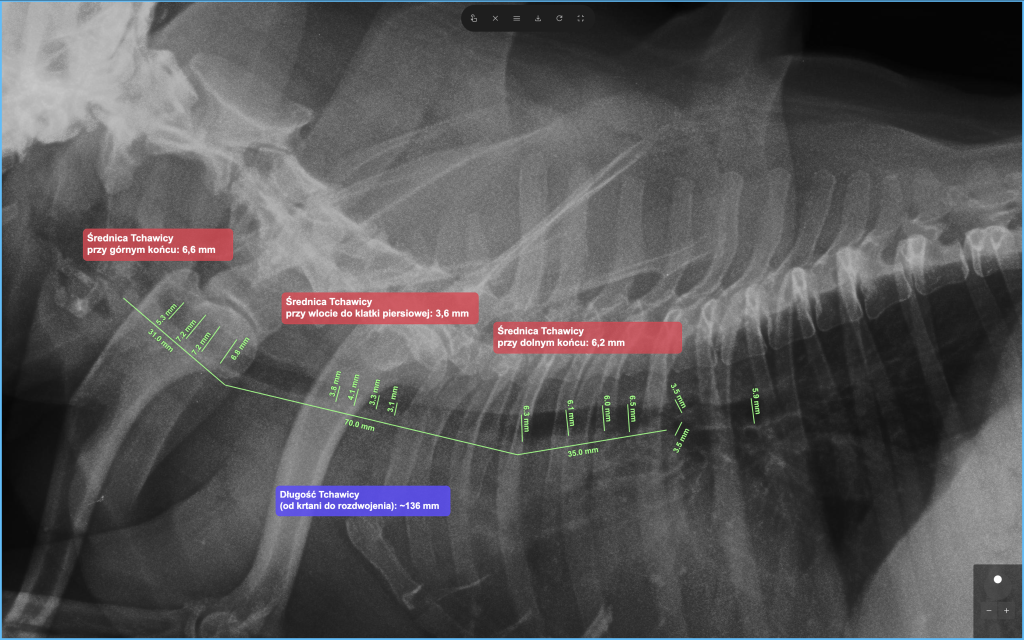

Stenty w leczeniu zwężenia tchawicy

Jednym z częstszych zastosowań stentów w medycynie weterynaryjnej jest leczenie zapadania się tchawicy (collapsus tracheae). Schorzenie to powoduje zwężenie światła tchawicy, co prowadzi do kaszlu i trudności w oddychaniu.

Wprowadzenie stentu do tchawicy stabilizuje jej ściany i umożliwia swobodniejszy przepływ powietrza.

Zakładanie stentu wykonywane jest zazwyczaj pod kontrolą diagnostyki obrazowej, takiej jak fluoroskopia, tomografia komputerowa lub endoskopia. Pozwala to na precyzyjne umieszczenie implantu w odpowiednim miejscu.